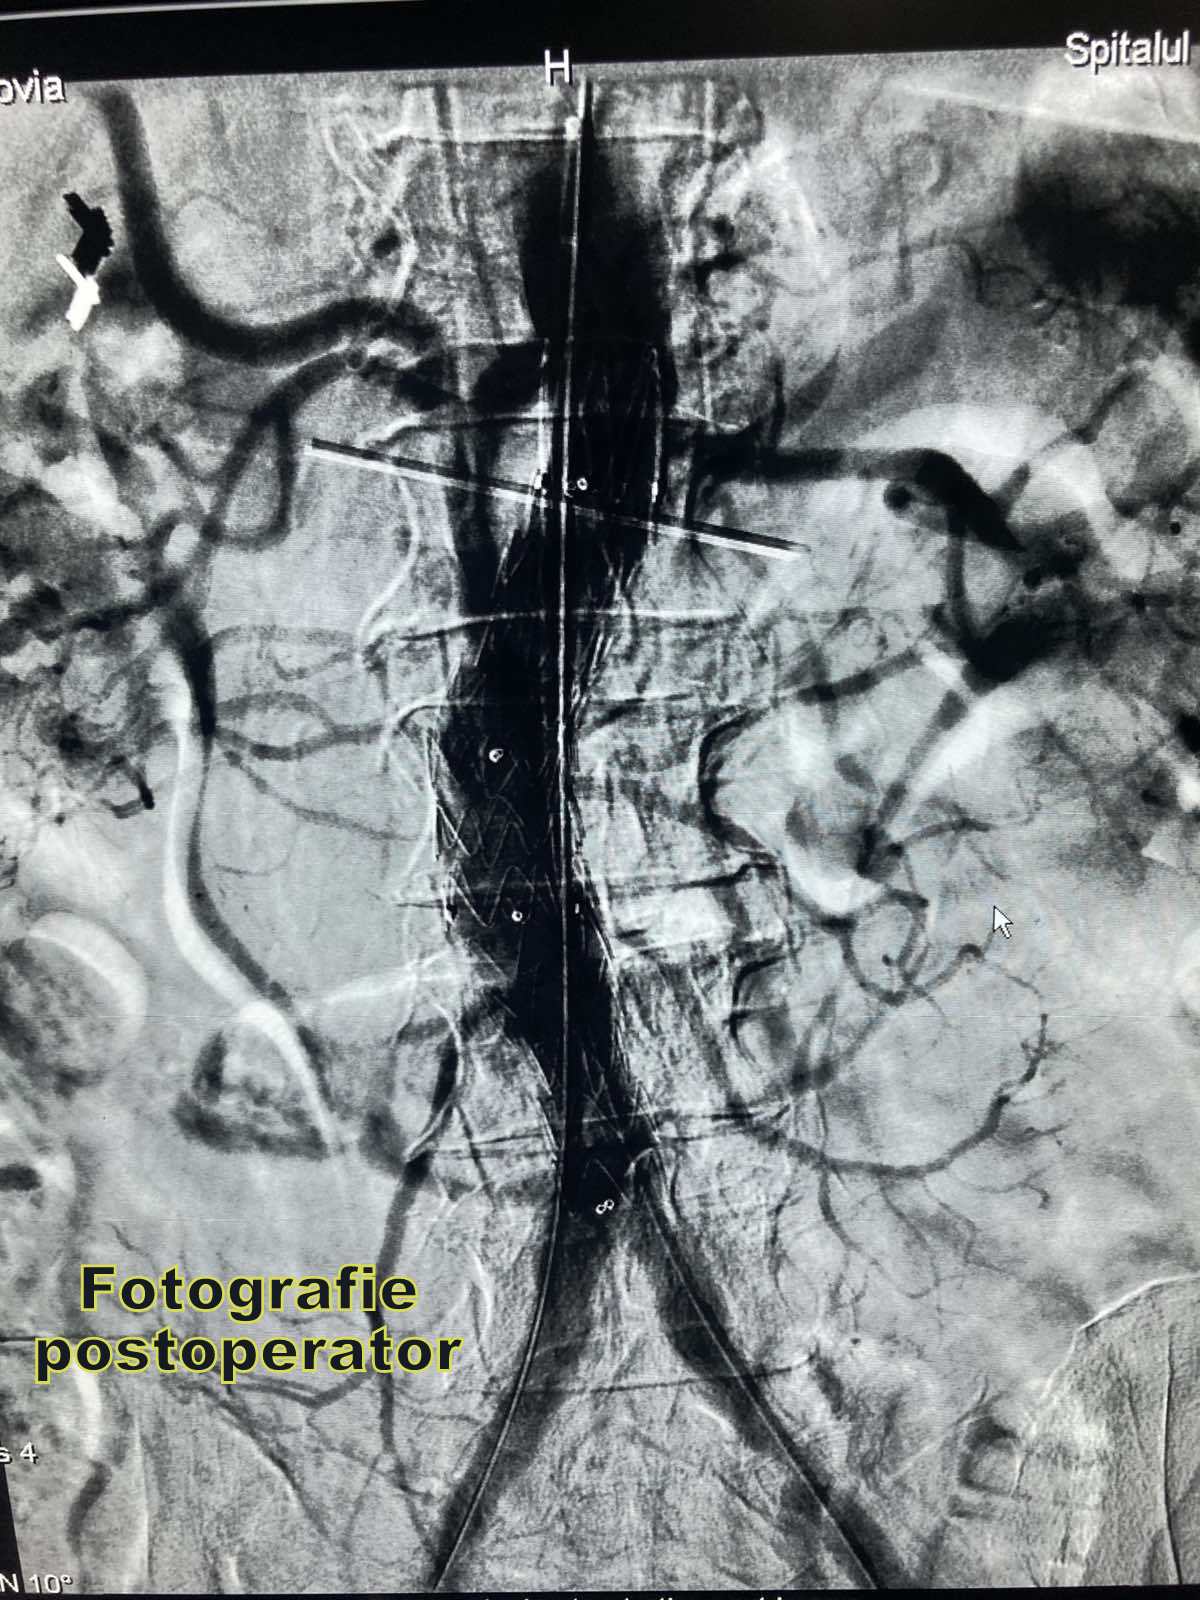

Metoda de endoprotezare a anevrismului de aortă, EVAR reprezintă o intervenție minim invazivă. Printr-o incizie mică la nivelul rădăcinei coapsei, endograftul pliat se avansează sub control radioscopic cu ajutorul unui ghid prin artera femurală în interiorul aortei dilatate, iar apoi cu ajutorul unor dispozitive speciale se distinge proteza și se fixează, acoperind în întregime anevrismul. Drept urmare sângele va circula în interiorul endograftului reducând presiunea de la nivelul pereților aortici, determinând în timp reducerea dimensiunilor anevrismuliu și scăderea riscului de ruptura aortică. Avantajele terapiei endovasculare a anevrismului de aortă sunt: incidența diminuată a complicațiilor majore preoperatorii, iar durata de spitalizare și perioada de recuperare sunt mult mai scurte (2-3 zile în comparație cu 7-10 zile).